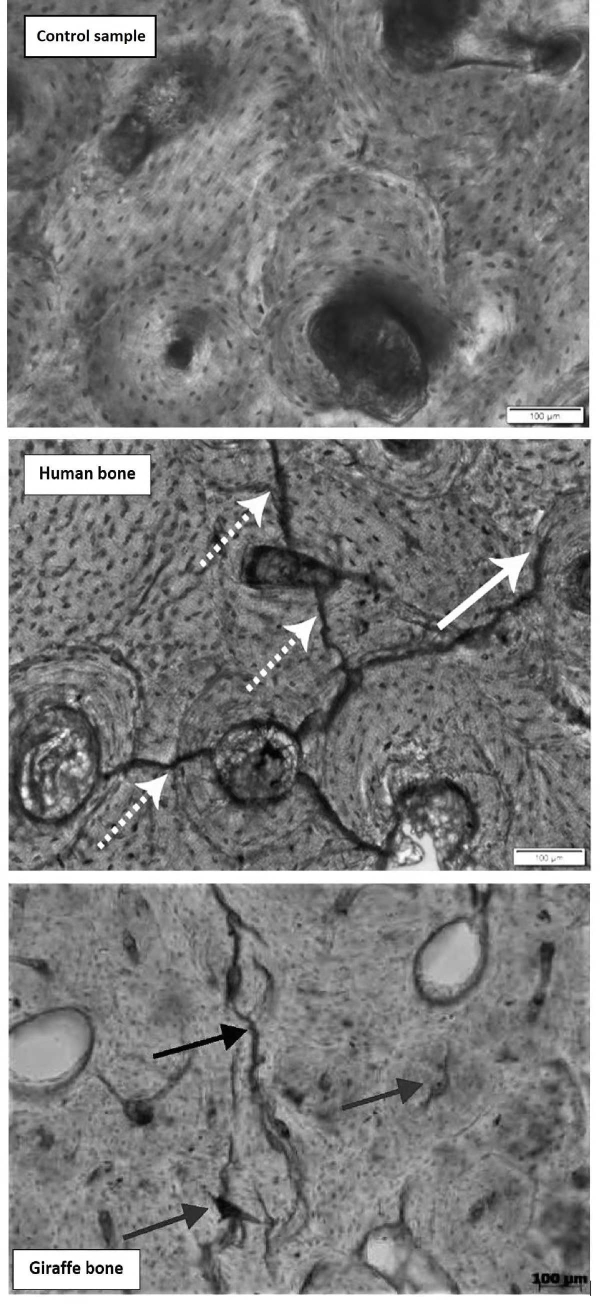

施加电流后,我们将骨头切成薄片,并使用光学显微镜和显微CT对其进行扫描成像。通过在细胞水平上观察骨骼,我们发现了一种特有的损伤模式,这是由短时间雷电流通过骨细胞所造成的。

这种损伤表现为从骨管中心向外辐射的裂缝,或在细胞簇之间不规则地跳跃的裂缝。整体损伤模式与其他高能量创伤(如在火中燃烧造成的创伤)非常不同。

我们在被自然闪电杀死的动物身上看到了同样的损伤模式。我们将人类的实验结果与已知被击中的野生长颈鹿的骨头进行了比较。尽管人骨的微观结构与长颈鹿骨有很大不同,但损伤的模式是相同的。